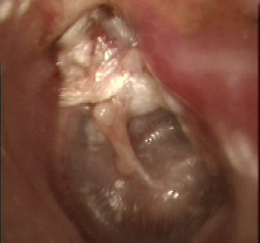

鼓膜に穴があいたままふさがらなくなり、聞こえが悪くなったり、ばい菌の感染を繰り返して耳漏(みみだれ)が出るのが、慢性中耳炎です。鼓膜をふさぐ方法には薬剤による最新の鼓膜再生法(リティンパ®、外来処置で行うもの)、接着法(湯浅法、短期入院で行う)、鼓膜(鼓室)形成術(基本的に全身麻酔、確実性が高い)がありますが、いずれの方法も対応可能です。鼓膜の状態によっても選択される方法が異なりますので、よく相談させていただき治療方針を決めてまいります。

最も重大な中耳炎が、真珠腫性中耳炎です。鼓室から上の部分、”鼓膜の屋根裏部屋“のほうにかけて真珠腫といわれる「垢のかたまり」のようなものが出来てしまい、周囲をゆっくり破壊しながら徐々に進行します(先天性のものなど、例外もあり)。鼓膜や、鼓膜の上側の骨がえぐれて、そこから病変が奥にすすんでいきます。この部分の骨の中には、聞こえやバランスの機能、顔を動かす神経などとても大事なものが組み込まれていますから、放置するとこれらが破壊されてしまい重大なことになります。

上のほうに行くと脳の入っている床の部分の骨(頭蓋底)が抜けおちてしまい、脳の神経の障害の原因になったりすることもあります。当科では、非常に細かい部分まで撮影できる最新のCTなどによって術前に精査を行い、手術によって病気をしっかり取り去り、本来の聞こえの構造と鼓膜をしっかり作り直す手術(鼓室形成術)を行います。手術は繊細で時間がかかる作業で、入院が必要です。手術後は削った空間にゴミや膿がたまりやすくなったりすることもありますので、定期的に耳の中をケアしていく作業を行います。手術の方法は、病状によっても異なりますので、その都度相談させていただき決定してまいります。